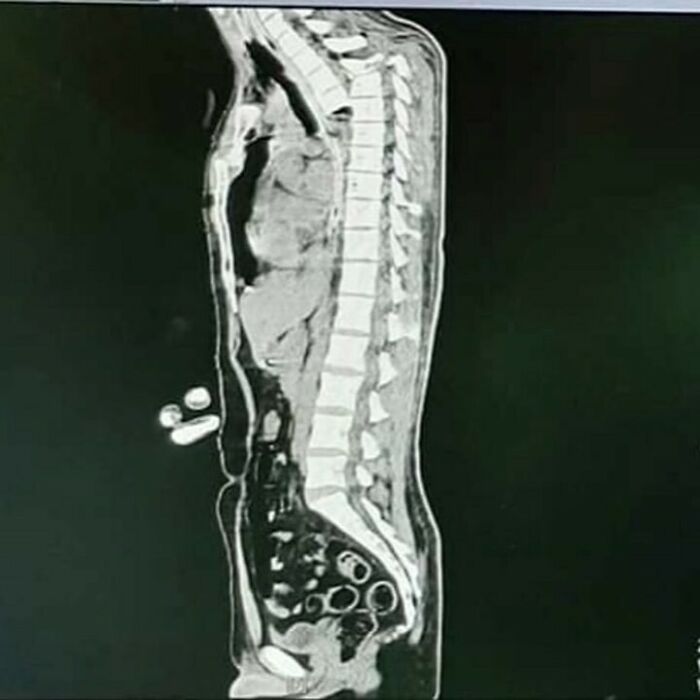

This is what constipation after 19 days looks like. A woman suffering from chronic constipation, discovers her colon severely displaced.

Image source: medical.doctors